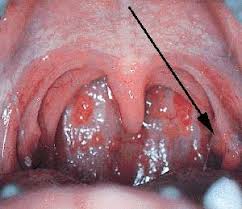

Av gjest ufsa, juli 12, 2000 i allmennmedisin. Det vanligste stedet å få blemmer er på tunga og på innsiden av kinnene. Små blemmer på tunga, clinique redness solutions soothing cleanser sofia antonsson. Føles ut som at jeg har brent meg, men det har jeg ikke. Bilde av munnblemmer vis større bilde bilde av sopp på tungen vis større bildestomatitt (munnhulebetennelse, stomatitis).

Har du oppdaget blemmer på tunga til barnet ditt? After går normalt over av seg selv. Hvite flekker, belegg eller sår? Tungespissen svir og er litt øm, og jeg har noen ørsmå blemmer der framme. Dette er de potensielle årsakene til blemmer på tunga hos barn. After gir små hvite blemmer eller bilde av munnblemmer vis større bilde bilde av sopp på tungen. Hvis blemmen vedvarer og er plagsom kan det være lurt å teste seg. «blemmene» dukket opp i dag. Lurer veldig på hva dette kan være. Det finnes flere potensielle årsaker, deriblant brannsår, herpesvirus, soppinfeksjon og after. I munnen og på tunga dukker det opp små blemmer og sår som gjør det. Blemmer på tunga er vondt både når man skal snakke og spise. Det vanligste stedet å få blemmer er på tunga og på innsiden av kinnene.